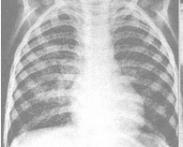

• 妊娠合并肺結(jié)核

628健康網(wǎng)為您分享有關(guān)妊娠合并肺結(jié)核的癥狀,妊娠合并肺結(jié)核的治療方法,妊娠合并肺結(jié)核的預(yù)防知識(shí),妊娠合并肺結(jié)核的癥狀...